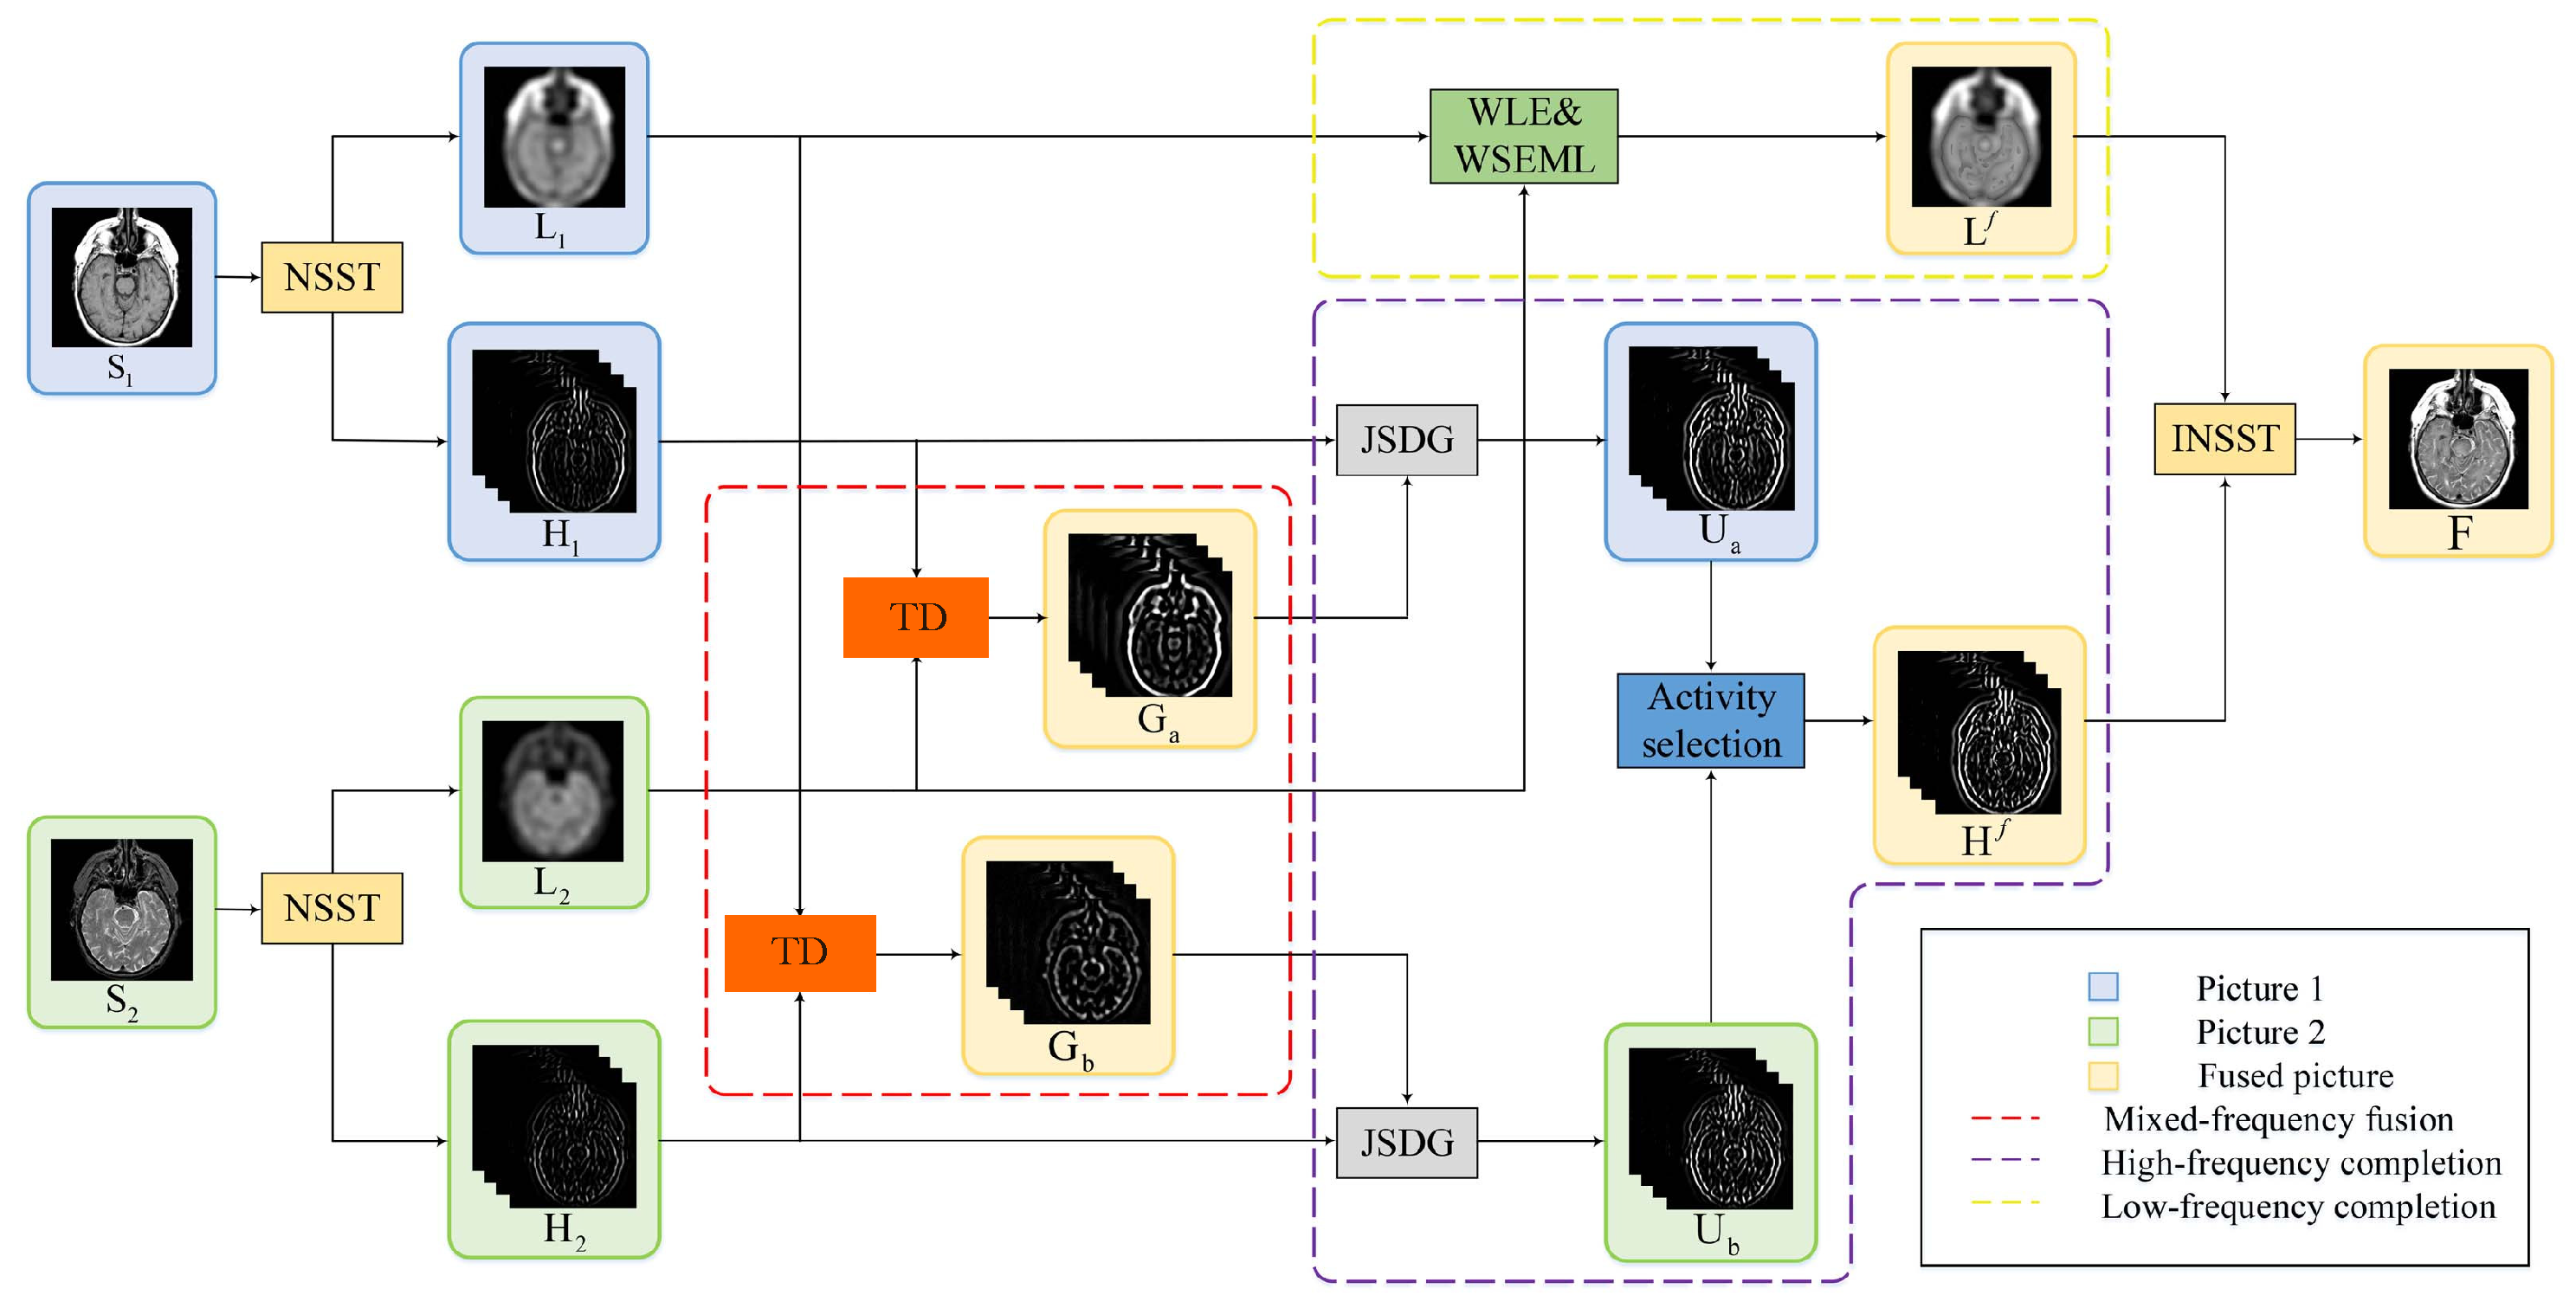

- Our TDFusion model is a unified optimization model. On the basis of the NSST method and the tensor decomposition method, the mixed-frequency fusion image is obtained by fusing the high-frequency and low-frequency components of two source images.

- Considering the structural differences between high-frequency and low-frequency components, some information will be lost during fusion. We embed the framework into the guided filter to optimize and complete the knowledge from low frequencies to high frequencies.

4. The Proposed Method

4.1. Nonsubsampled Shearlet Transform (NSST)

4.2. Tensor Decomposition Based Fusion

4.3. The Optimization Solution

4.4. High-Frequency Completion

4.4.1. Joint Static and Dynamic Guidance

4.4.2. Fusion of Complete Mixed-Frequency Maps

4.5. Low-Frequency Completion

4.6. Reconstruction Fused Image by the INSST